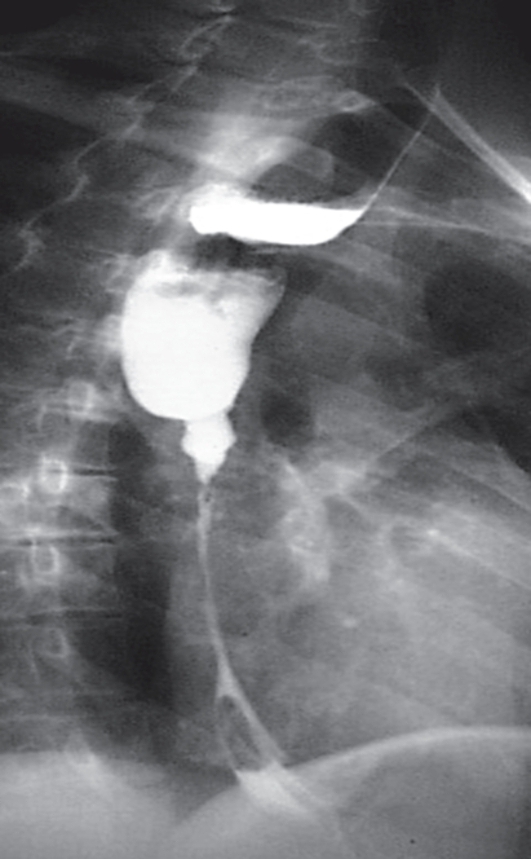

Больная, 29 лет, жалуется на выраженную дисфагию (проходит только вода), общую слабость, похудение, повышенную саливацию. Год назад с суицидальной целью выпила уксусную эссенцию. Первая помощь была оказана дома, затем в стационаре. Из больницы выписана через 1 мес в удовлетворительном состоянии, пища по пищеводу проходила свободно. Через 3 мес после выписки возникла дисфагия, которая прогрессирующе усиливается. Больная похудела на 11 кг. Рентгенологически выявлена следующая картина (рис. 27).

Рис. 27.Рентгенограмма пищевода больной, 29 лет